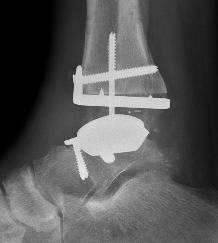

CT

Evaluate bone stock to determine if TAR is appropriate

Talar dome resurfacing

- jig to make chamfer cuts

Insert mobile / fixed bearing